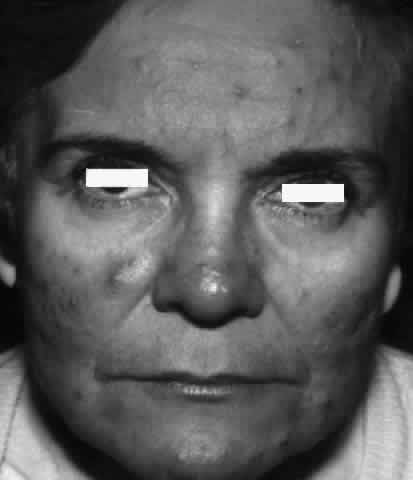

Pemphigus (from the Greek meaning puff or blister) comprises a group of autoimmune vesiculobullous eruptions of the skin and mucous membranes that are seen primarily in middle-aged people, with both sexes being affected equally.3 Involvement of mucosae may occur as the initial manifestation in as many as 25% of cases, and it occurs at some point during the course of disease in 95% of cases.4 Pemphigus vulgaris and its variant, pemphigus vegetans, constitute a more acute form of the disease in which the earliest lesions appear in the oral mucosa and are then followed by a bullous eruption of the skin over the trunk and extremities within 4 to 12 months (Fig. 1). This form of pemphigus was almost uniformly fatal prior to the use of systemic corticosteroid therapy. The mortality rate was reduced to approximately 40% by the use of steroids and has been further reduced to 5% by the addition of immunosuppressive chemotherapeutic regimens for the most difficult cases. Pemphigus foliaceus and its variant, pemphigus erythematosus, follow a more chronic but benign course. Mucosal lesions are unusual in this form, which is primarily an exfoliative dermatitis.3